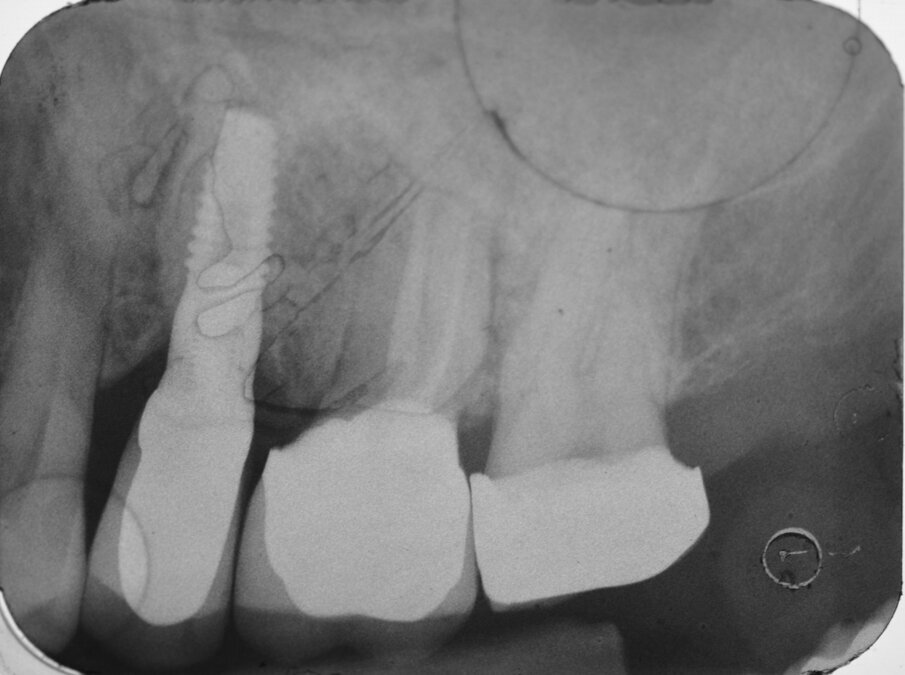

Paziente di aa 56, maschio, giunge alla nostra osservazione lamentando dolorabilità alla palpazione e alla masticazione in corrispondenza dell’elemento 1.6 sottoposto a terapia endodontica diversi anni prima. All’esame obiettivo si rileva la presenza di un’ampia raccolta ascessuale vestibolare associata a una profonda lesione parodontale nella zona della forcazione radicolare buccale (Fig. 1). Il sondaggio nel resto del cavo orale non evidenzia la presenza di altre lesioni parodontali (Fig. 2) mentre l’indagine radiografica rivela la presenza di un’ampia area di radiotrasparenza che coinvolge tutto lo spazio periapicale a partenza dalla radice mesio-buccale (Fig. 3). Sulla base dei dati clinici e radiografici acquisiti viene pertanto confermata la diagnosi di lesione endo-parodontale; nello specifico, si tratta di una lesione endodontica primaria con secondario interessamento parodontale e coinvolgimento della forcazione radicolare di Classe 3 secondo Hamp & Nyman3.

Fig. 3 - Esame CBCT preoperatorio (sezione sagittale).